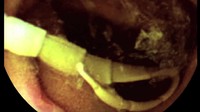

Cacing pita dipilih karena relatif lebih aman dibandingkan parasit lain. Foto ini misalnya menunjukkan ujung dari cacing pita memiliki empat buah penghisap yang digunakan untuk menempel di usus, bukan seperti gigi atau cakar tajam yang bisa melukai dinding usus. (Foto: Youtube/BBC)